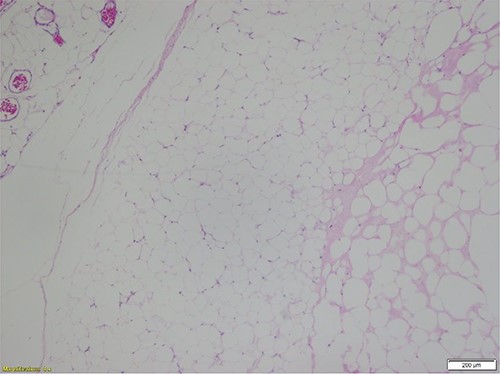

Histopathologic evaluation of representative hematoxylin and eosin (H&E)-stained sections from each specimen were similar and showed mature adipocytes of typically uniform size with foci of degeneration of fat necrosis. Adipocytes did show varying sizes in these regions of necrosis and degeneration. The tumors exhibited the typical fibrous septal vascularity of mature, benign lipomas. Rarely, focal microcalcifications are seen in areas of fat necrosis with degenerative adipocyte changes (Figs 1 and 2).

Mature adipocytes of a benign lipoma with relatively scant, septal vascularity and foci of fat necrosis (H&E-stained section; ×40 total magnification: ×4 objective with ×10 ocular lens) (Courtesy Karl Biesemier, MD. Pathology Consultants of Central Virginia, Lynchburg, VA).